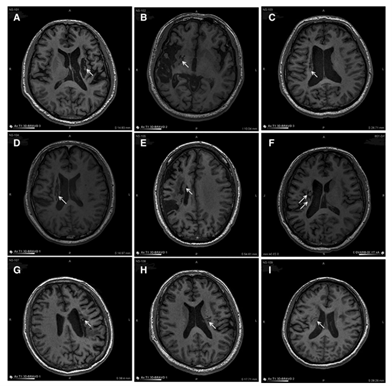

解放军总医院在《干细胞转化医学》杂志上公布了一项研究:9 名 30-65 岁的脑卒中偏瘫患者,在中风后 5-24 个月接受了人源神经干细胞 NSI-566 的脑内回输(注入梗塞灶附近)。经过 24 个月随访,影像学显示干细胞植入区长出了新的神经组织;

更重要的是,9 名患者的偏瘫症状均明显改善 —— 这得益于干细胞分化为神经细胞、分泌营养因子、促进神经和血管再生的综合作用。